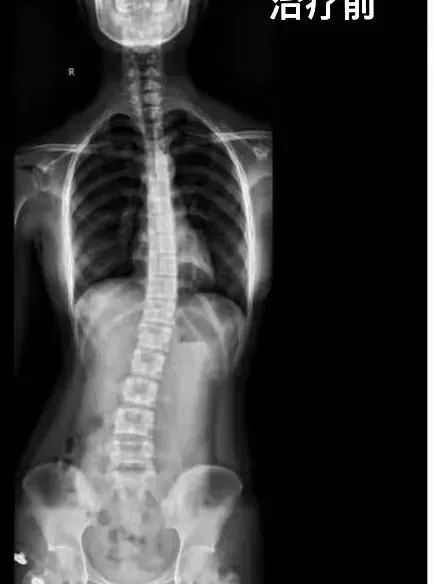

脊柱侧弯80度图片

15岁的小时同学该患者8岁时出现轻度脊柱侧弯,但家长未重视